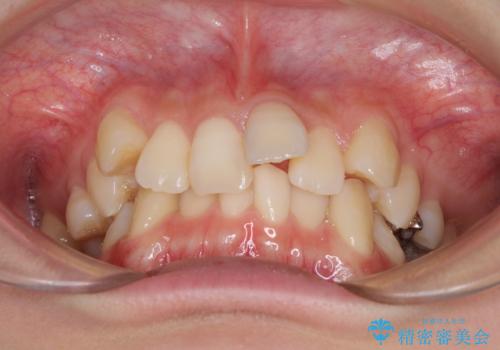

- 前歯の叢生と八重歯を気にして来院された患者様です。

叢生が強く、奥歯の咬合も左右差が大きかったため、上下左右4本を抜歯して、ワイヤー矯正を行うこととしました。